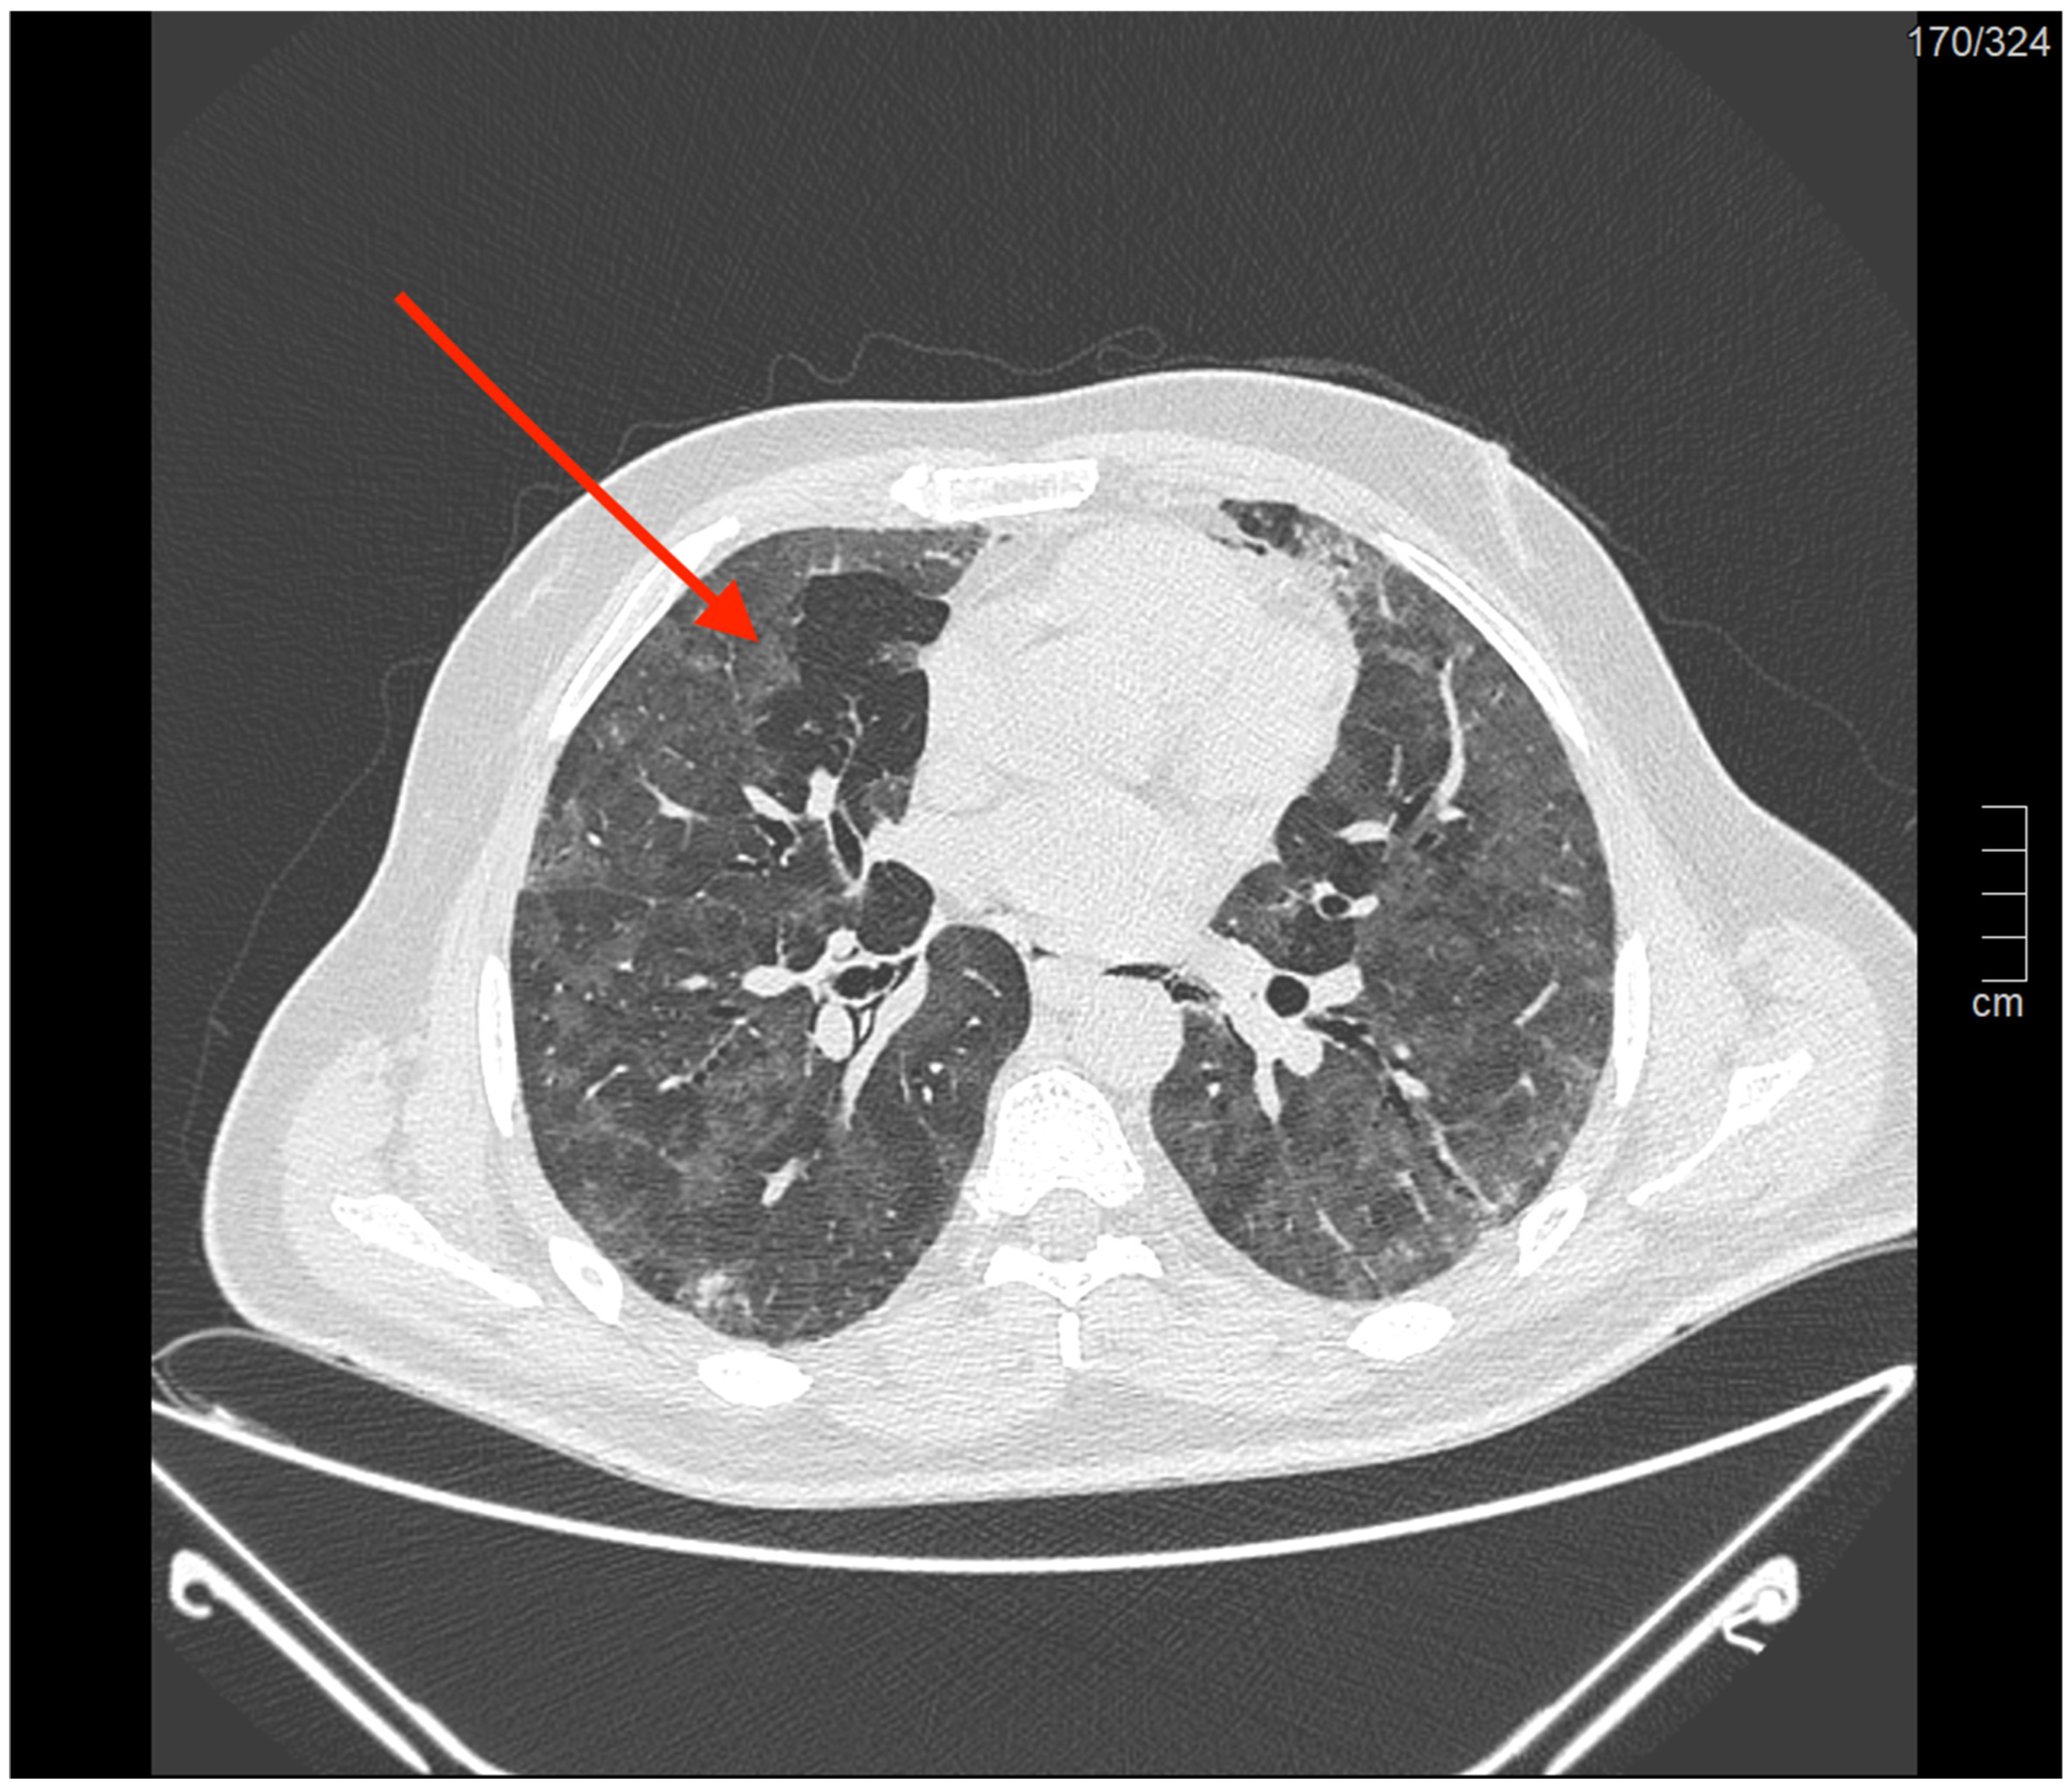

- Paternoster, G.; Belmonte, G.; Scarano, E.; Rotondo, P.; Palumbo, D.; Belletti, A.; Corradi, F.; Bertini, P.; Landoni, G.; Guarracino, F.; et al. Macklin Effect on Baseline Chest CT Scan Accurately Predicts Barotrauma in COVID-19 Patients. Respir. Med. 2022, 197, 106853. [Google Scholar] [CrossRef] [PubMed]

- Belletti, A.; Pallanch, O.; Bonizzoni, M.A.; Guidi, L.; Cobelli, F.D.; Landoni, G.; Zangrillo, A.; Bonis, M.D.; Palumbo, D. Clinical Use of Macklin-like Radiological Sign (Macklin Effect): A Systematic Review. Respir. Med. 2023, 210, 107178. [Google Scholar] [CrossRef] [PubMed]

- Maccarrone, V.; Liou, C.; D’souza, B.; Salvatore, M.M.; Leb, J.; Belletti, A.; Palumbo, D.; Landoni, G.; Capaccione, K.M. The Macklin Effect Closely Correlates with Pneumomediastinum in Acutely Ill Intubated Patients with COVID-19 Infection. Clin. Imaging 2023, 97, 50–54. [Google Scholar] [CrossRef] [PubMed]

- Casadiego Monachello, F.J.; de la Torre Terron, M.C.; Mendez Barraza, J.A.; Casals Vila, S. Macklin Effect as an Early Radiological Predictor of Barotrauma in ARDS COVID-19 Patients in Invasive Mechanical Ventilation. Med. Intensiv. 2023, 47, 235–236. [Google Scholar] [CrossRef]